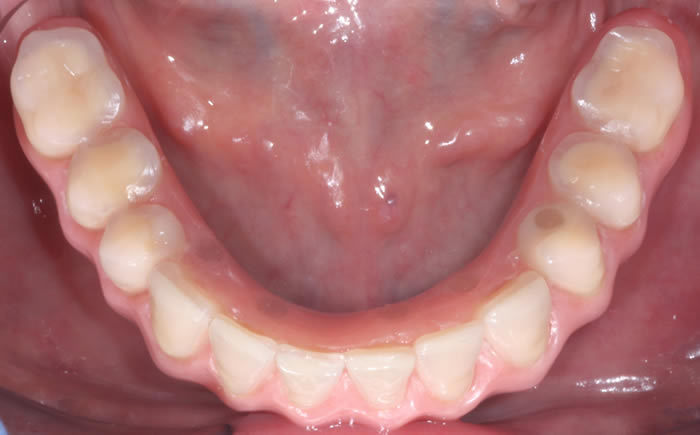

Back teeth replaced by dental implants

Case One (3 images)

Missing lower teeth replaced by three dental implants and crowns.